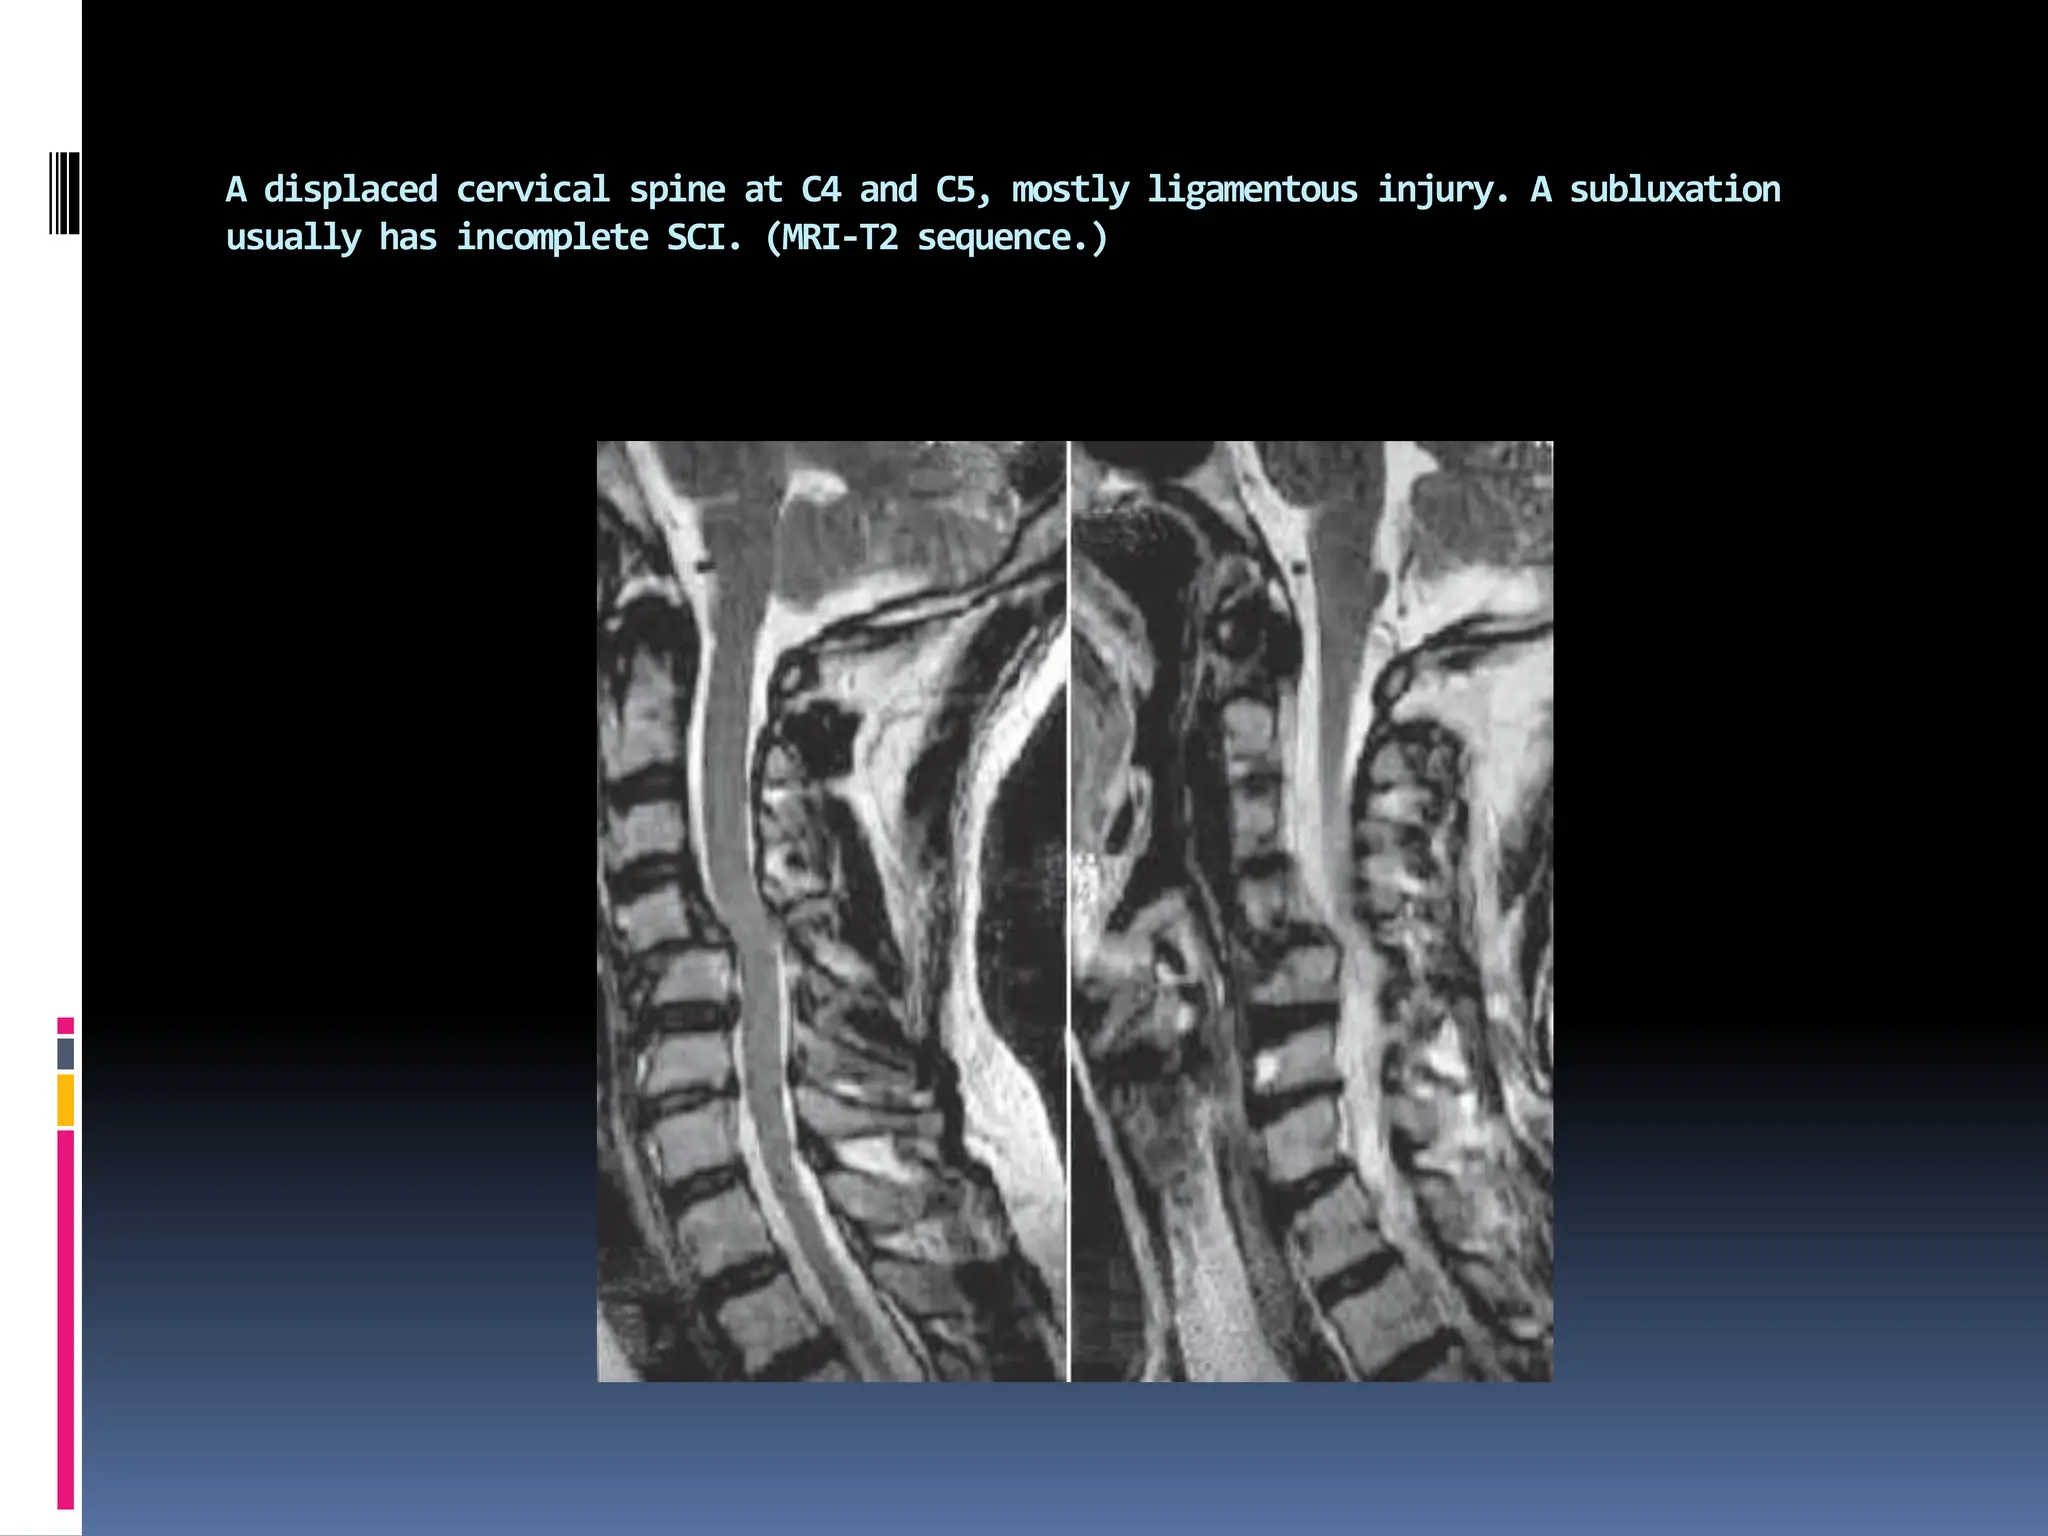

A displaced cervical spine at C4 and C5, mostly ligamentous injury. A subluxation

usually has incomplete SCI. (MRI-T2 sequence.)